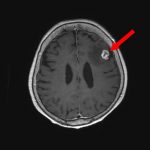

手術前1

手術前2